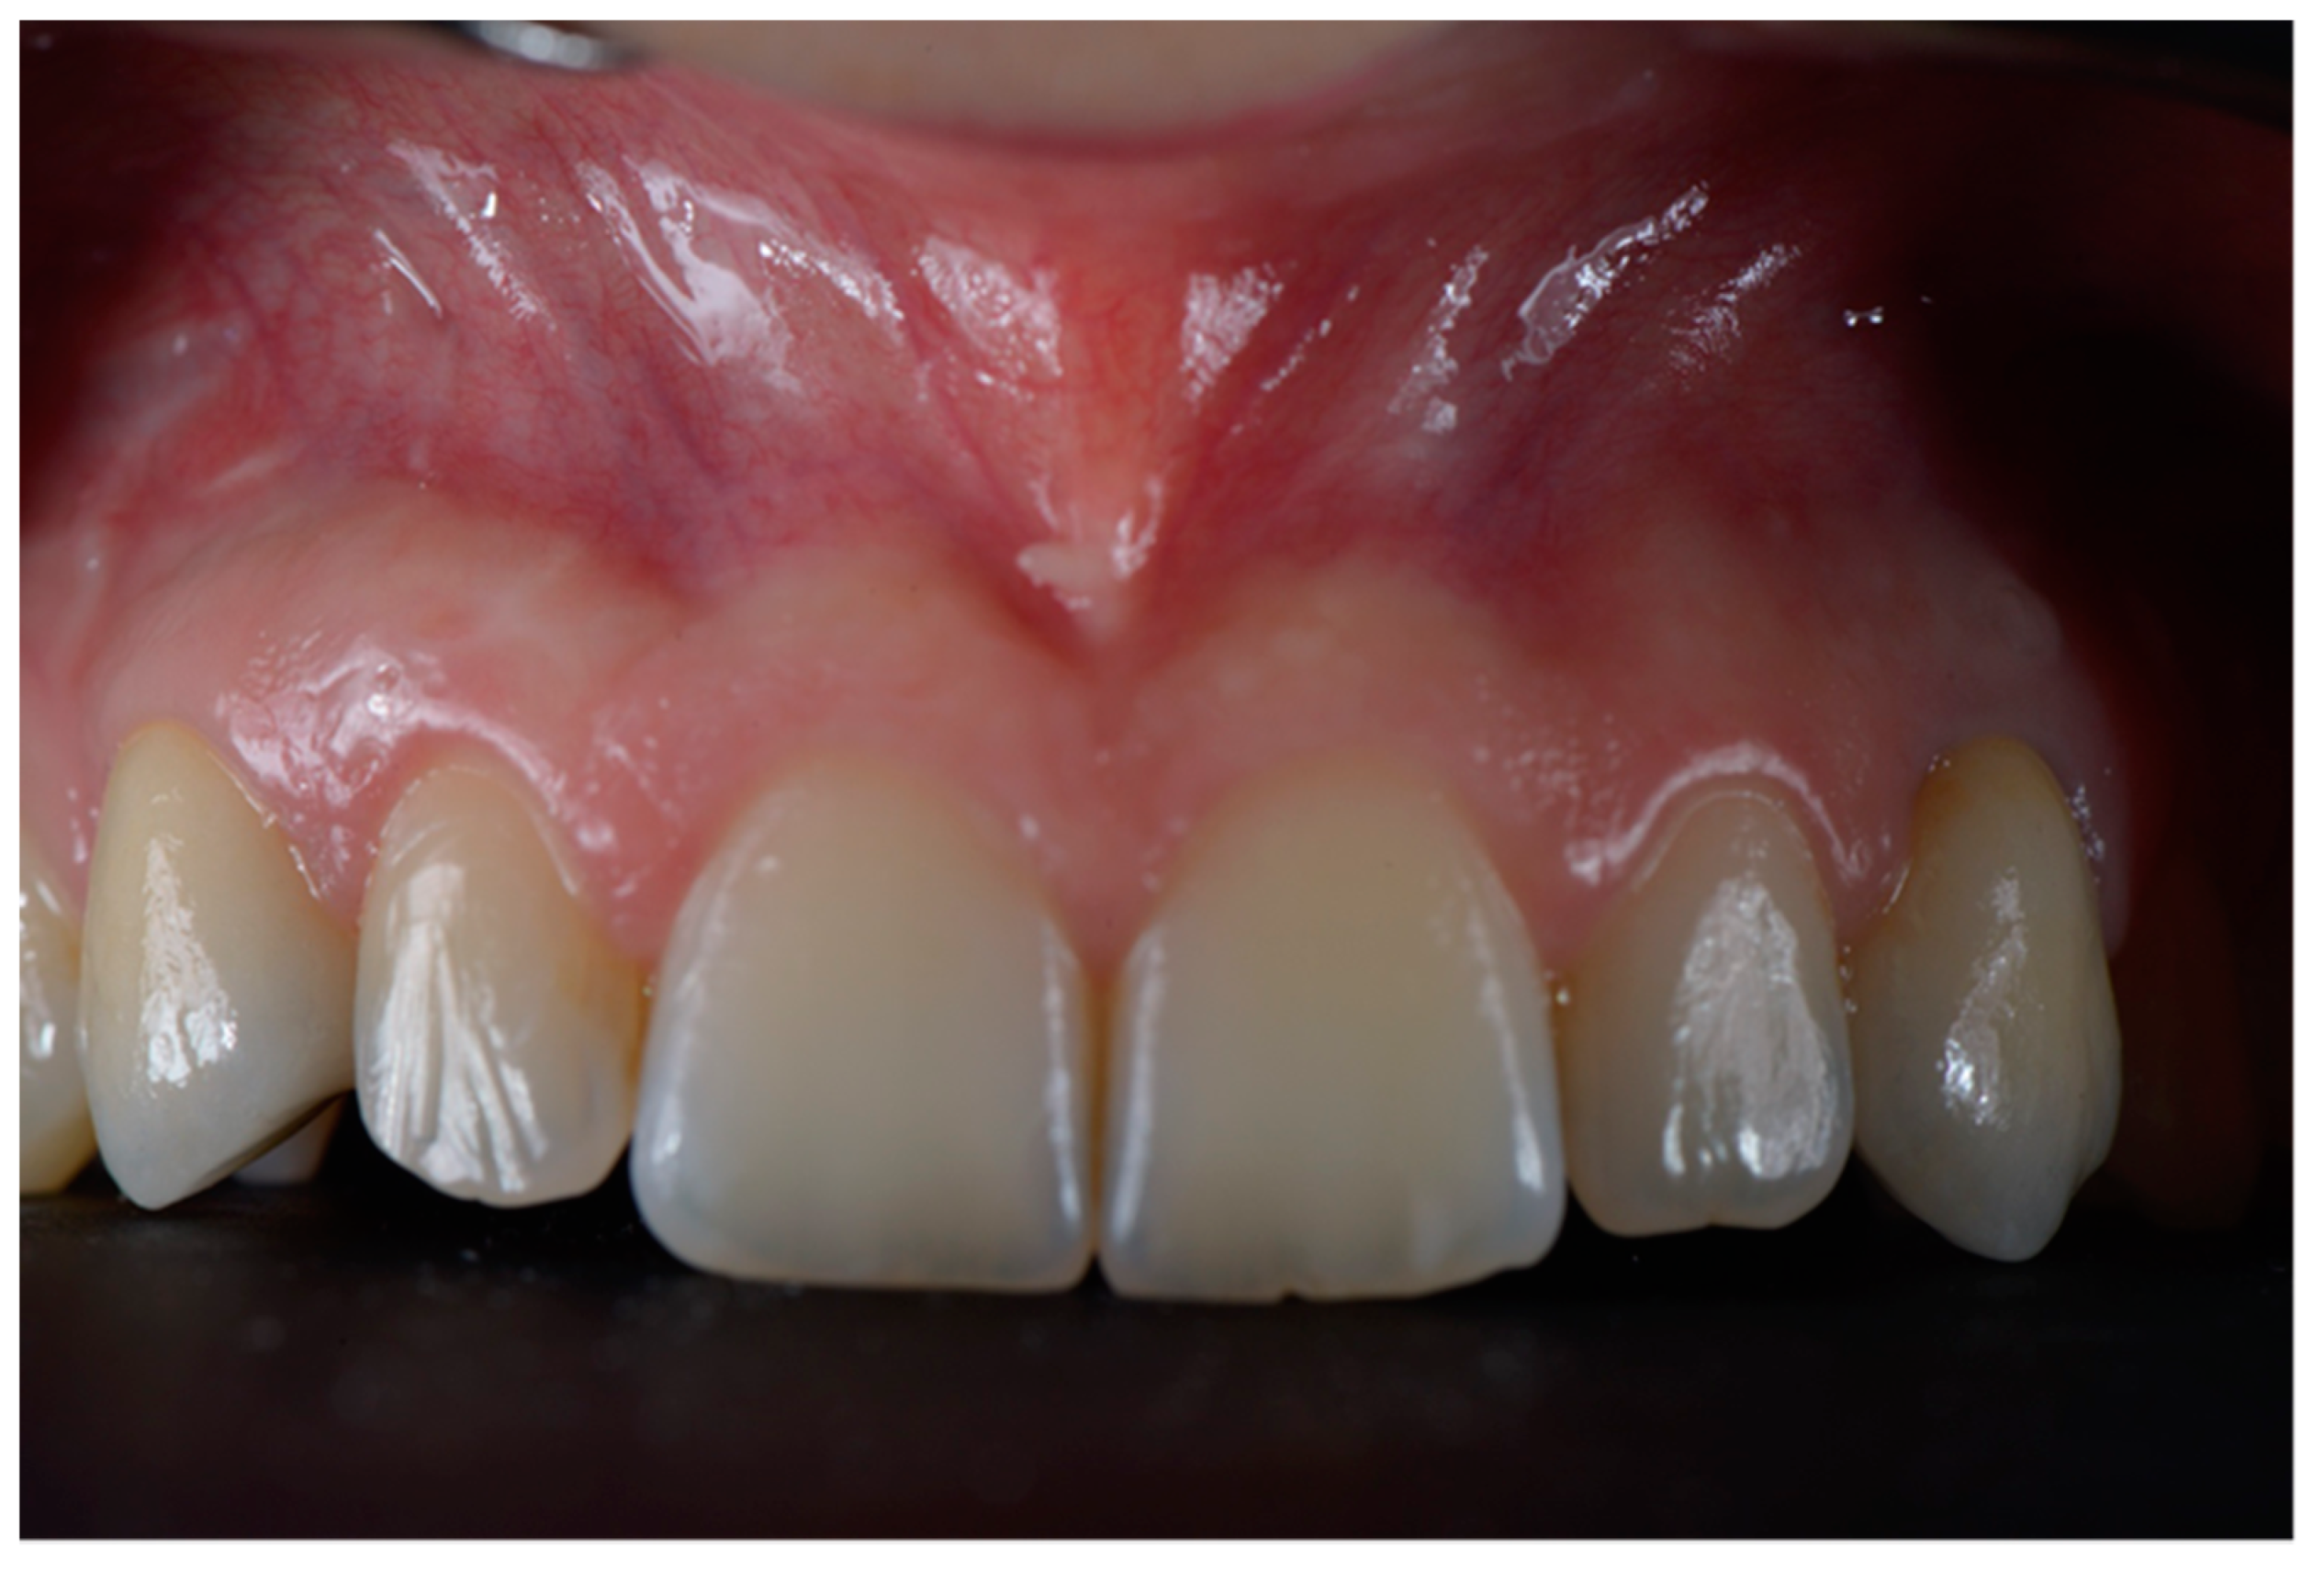

2.3. Surgical and Prosthetic Workflow

2.4. Outcome

3. Results